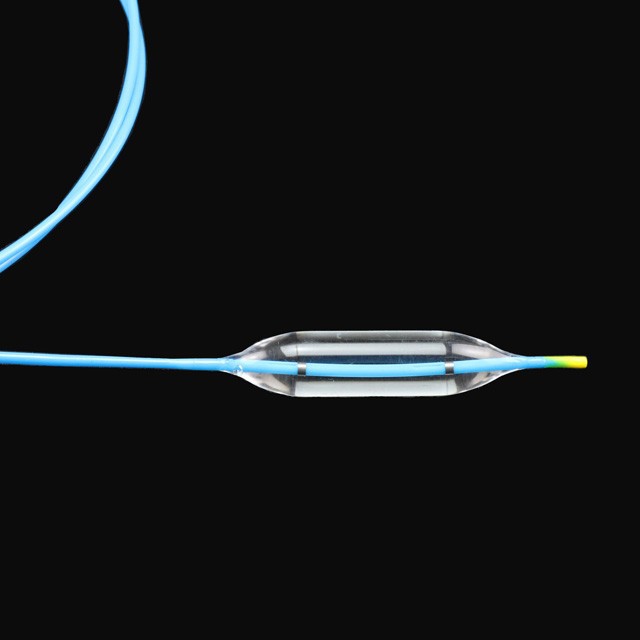

● Elastic yakapfava tip dhizaini, iyo inogona kupinda mukati medu pachinzvimbo chakanangana nechinzvimbo chisina kukuvara {}

● Kugadzira kurongeka kwehubhu kunoita kuti zvive zvatakapfidza uye nezvakanaka zvakanaka, zvinokatyamadza kupokana nekukasira uye kupfuudza nyore nyore .

● Iyo adigaque mamaki pamigumo miviri yeballoon inogona kupa chaiyo chinzvimbo pasi pe x-ray .

● Pre-input 0 . 035 "kutungamira waya neye nyoro nyoro uye mucherechedzo, iri nyore kufungidzira urefu hwemukati wemukati waya.